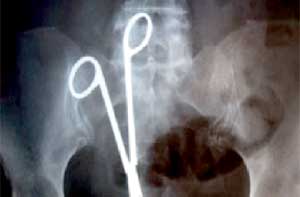

طبيبة تروي معايشتها معاناة مريضة..الأخطاء الطبية كثير من الإهمال... قليل من الصحة